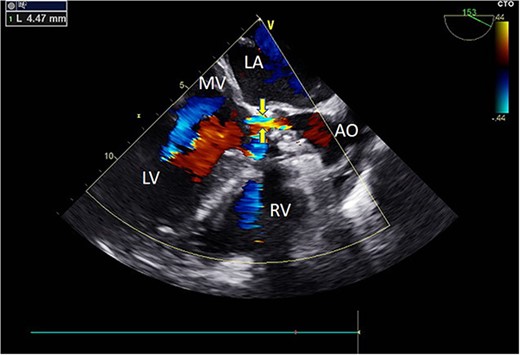

Intraoperatively, after self-expanding the aortic valve, TEE monitoring confirmed excellent cardiac function, disappearance of aortic valve regurgitation, secure anchoring of the aortic valve prosthesis, and no obstruction to the mitral valve leaflets or coronary ostia. The aortic valve velocity and pressure gradient upstream of the valve decreased compared to preoperative values, with a maximum velocity of 166 cm/s and a pressure gradient of 11 mmHg (Fig. 3). However, a periprosthetic leak with a residual width of ~4.5 mm was observed at the self-expanding valve’s interface with the native annulus (Fig. 4). Based on preoperative data, the decision was made to re-expand and reshape the prosthesis. Postdilation, TEE monitoring showed a reduction in the periprosthetic leak to 1.5 mm (Fig. 5), a significant improvement compared to predilation. Following satisfactory self-expansion results, the planned percutaneous ASD closure procedure was performed under ultrasound guidance. The closure device was securely positioned in the atrial septum, and TEE examination showed no deformation or impingement of the self-expanding valve (Fig. 6). Atrial shunting was eliminated, and the outcome exceeded expectations.

Intraoperative TEE: Long-axis aortic view displays a 4.5 mm-wide perivalvular blood flow bundle around the aortic valve (arrow). Abbreviations: LA - left atrium; LV - left ventricle; RV - right ventricle; AO - aortic.

Intraoperative TEE: Long-axis aorta section shows a 1.5 mm-wide paravalvular blood flow beam, demonstrating significant improvement. Abbreviations: LA - left atrium; LV - left ventricle; RV - right ventricle; AO - aorta; MV - mitral valve.